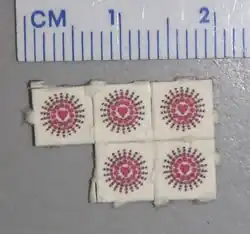

Psychedelika und Halluzinogene

Als Psychedelika (zusammengesetzt aus altgriechisch ψυχη psychḗ‚ Seele‘ und δῆλος dẽlos ‚offenkundig, offenbar‘) werden psychotrope Substanzen bezeichnet, die als potente Agonisten der Serotonin-Rezeptoren 5-HT2A/2C wirksam sind.[100][101] Der Begriff ging 1956 aus einem Briefwechsel des Psychiaters Humphry Osmond mit dem Schriftsteller Aldous Huxley hervor.[102] Der Duden definiert psychedelisch wie folgt: „das Bewusstsein verändernd; einen euphorischen, tranceartigen Gemütszustand hervorrufend“.[103] Der Beipackzettel des Psychedelikums Delysid (LSD), welches 1949 auf den Markt kam, wies auf die Möglichkeit der Anwendung als Psycholytikum und Psychotomimetikum hin. Textauszug Indikation: „(a) In der analytischen Psychotherapie zur Förderung seelischer Entspannung durch Freisetzung verdrängten Materials. (b) Experimentelle Studien über das Wesen der Psychose: Indem der Psychiater selbst Delysid einnimmt, wird er in die Lage versetzt, eine Einsicht in die Welt der Ideen und Wahrnehmungen psychiatrischer Patienten zu gewinnen.“[104] Die Intoxikation mit psychedelischen Zuständen wird Trip genannt, der klinische Überbegriff der Psychedelika wird Halluzinogene genannt; mögliche medizinische Anwendungen werden diskutiert.[105][106][107] Zu den Psychedelika gehören:

DOB-Blotter

DOB-Blotter